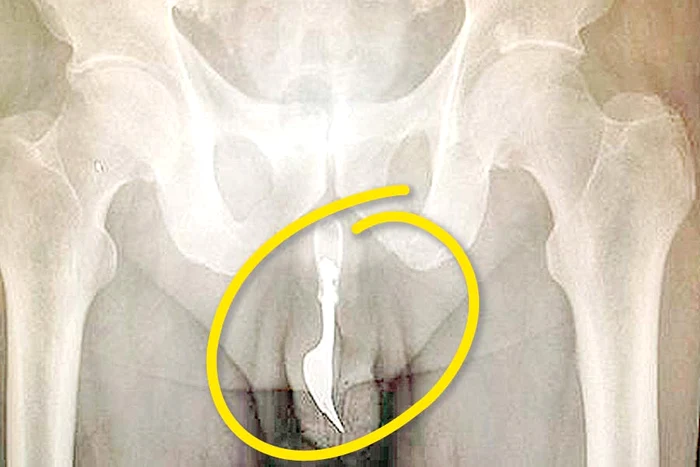

Un caz incredibil de bizar a fost raportat de o echipă de medici din Australia: un bărbat în vârstă de 70 de ani a ajuns la spital după ce şi-a introdus în penis o furculiţă lungă de 10 centimetri.

Medicii de la spitalul Canberra susţin că nu au mai văzut aşa ceva vreodată şi că au fot nevoiţi să îl opereze pe om pentru a-l scăpa de «povară». «Am încercat mai multe metode de extragere a furculiţei şi până la urmă a trebuit să folosim un forceps. Organul sexual a trebuit să fie lubrifiat intens şi cu siguranţă bărbatul a simţit o durere enormă. Astfel de cazuri se întâlnesc numai atunci când este vorba despre pacienţi care suferă de afecţtiuni cronice manifestate prin masturbare excesivă, patologică», a explicat unul din medici.